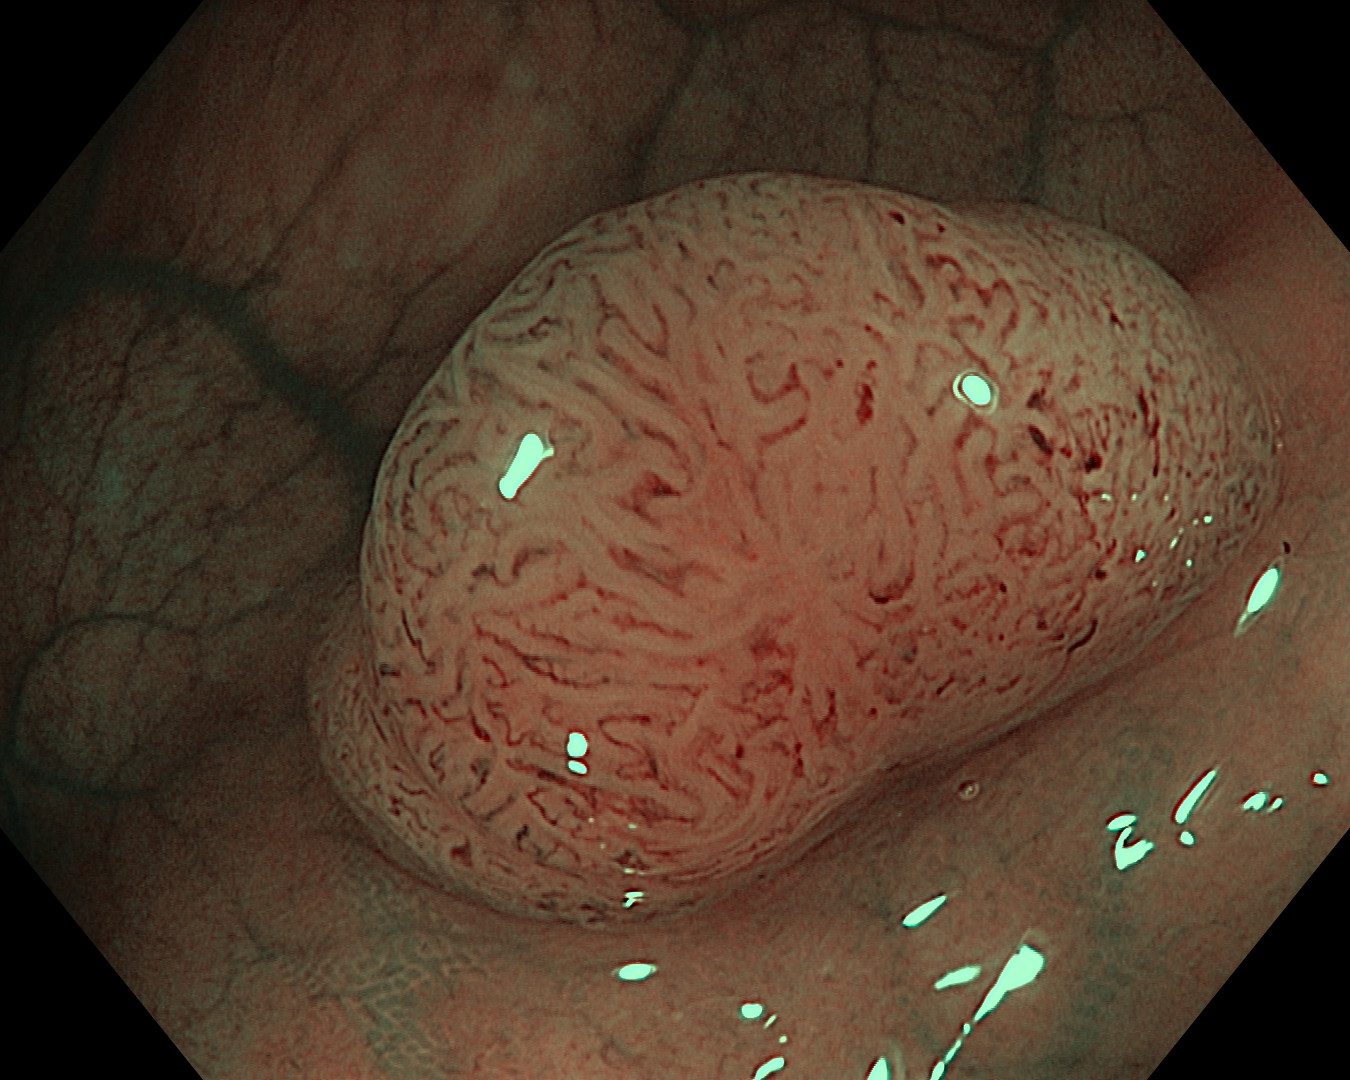

Prikaz polipa kolona u uskopojasnom spektru s uvećanjem

| Resekcijsko mjesto nakon uklanjanja polipa (polipektomija) |